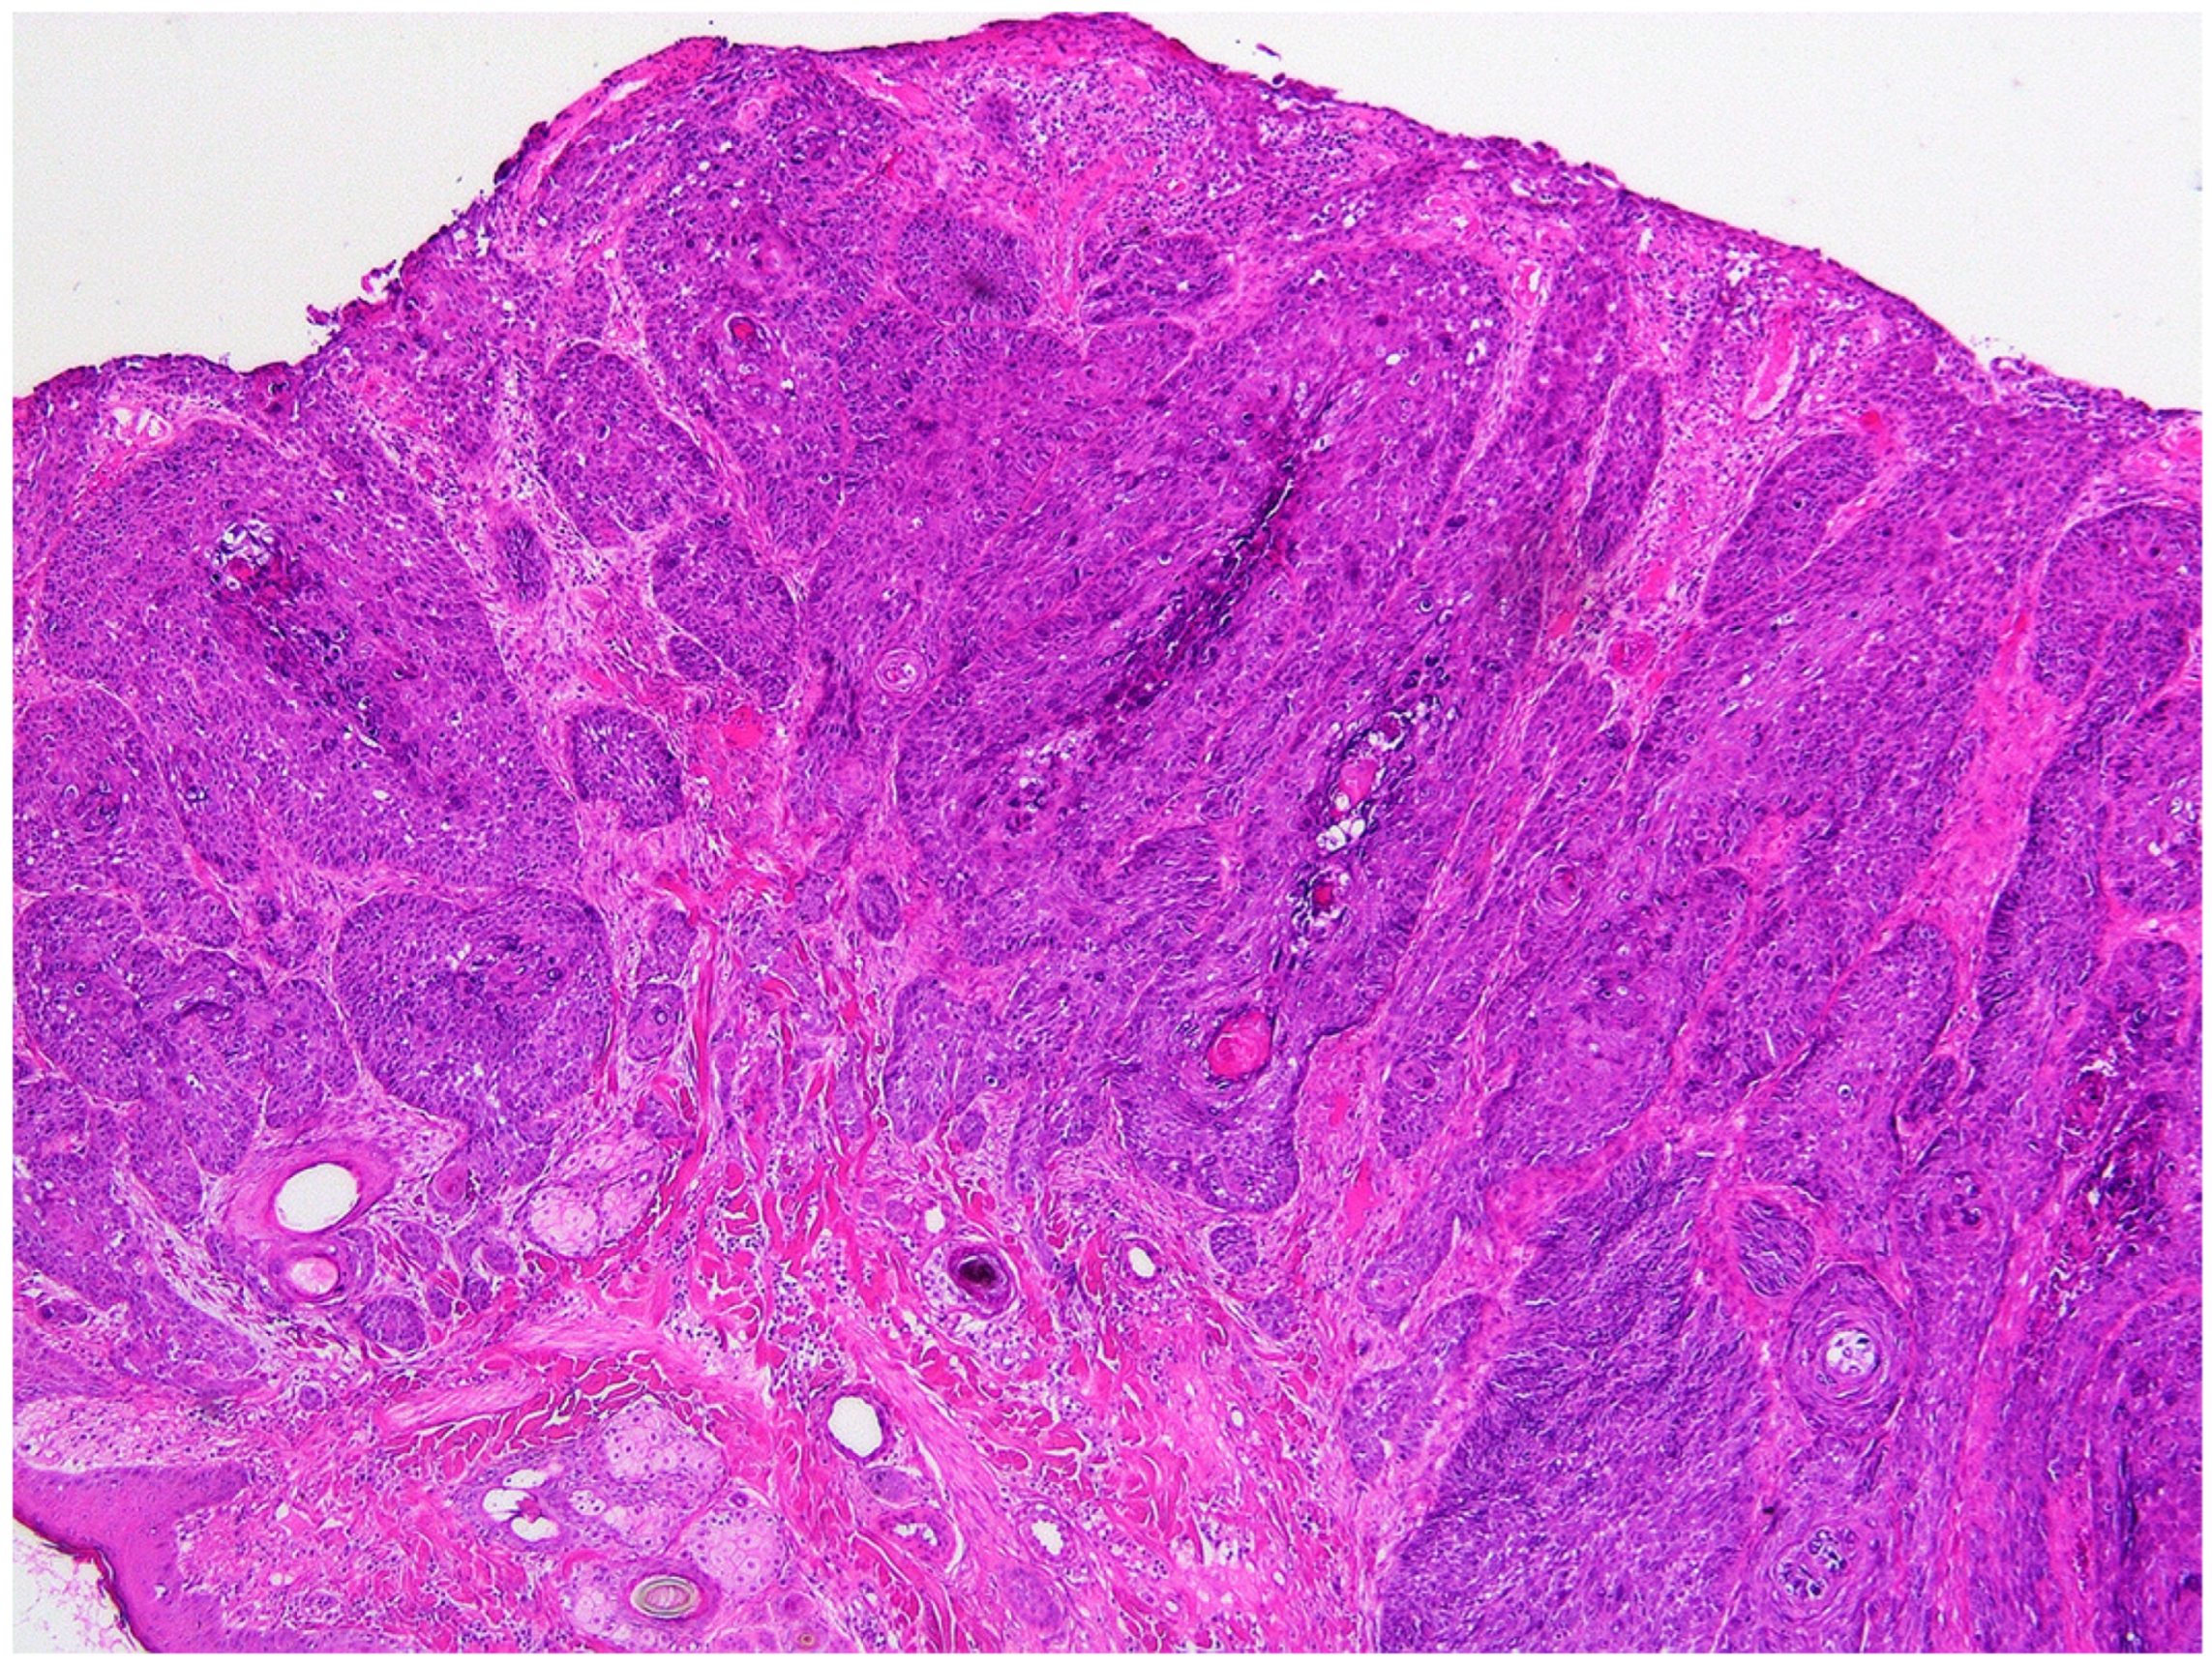

2. Case Presentation and Diagnosis